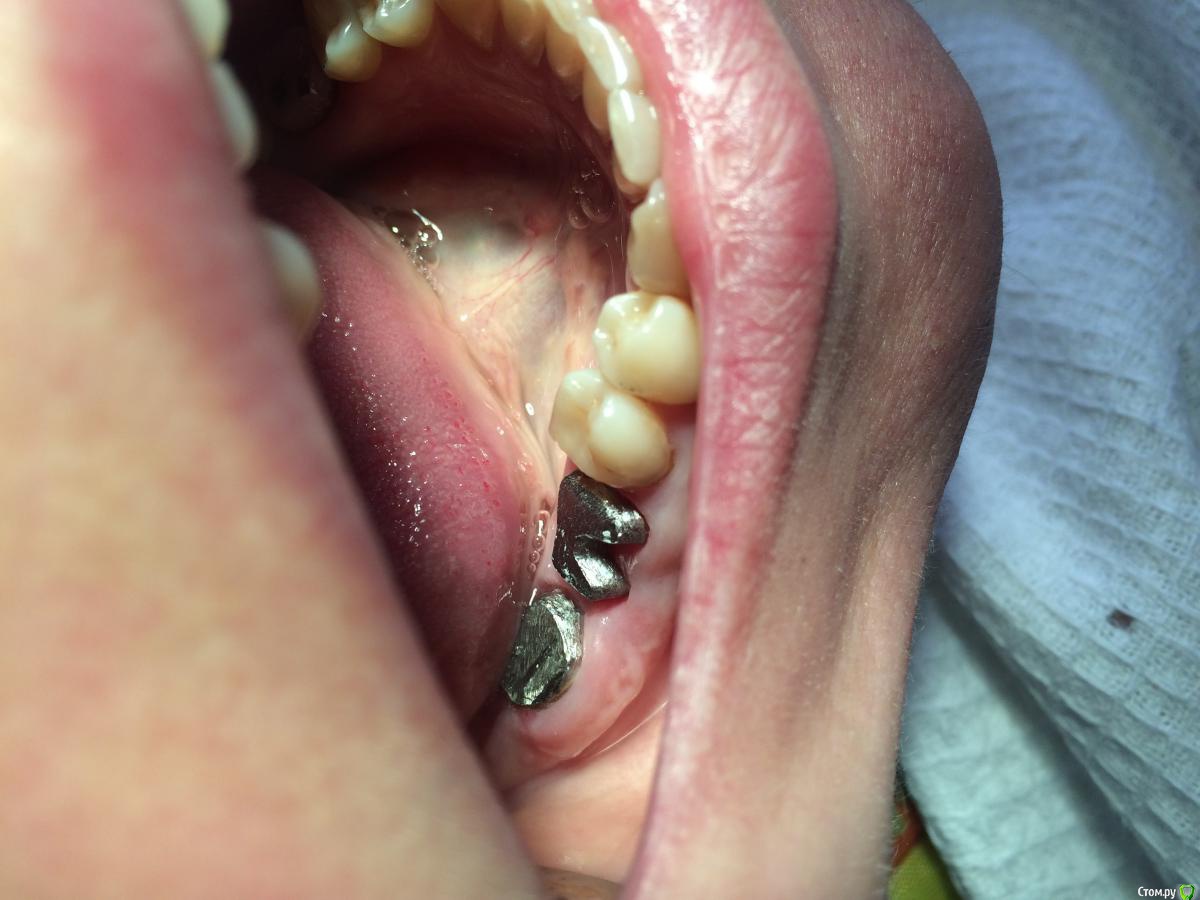

Danger Опубликовано 17 октября, 2016 Поделиться Опубликовано 17 октября, 2016 17 зуб. С дистальной стороны убрал десну для визуализации и весь некротический дентин.пациентка имплантацию не потянет, а у меня желания ставить мост на шаткий 18 вовсе нет( Реально ли такой восстановить? Ссылка на комментарий

dentikl Опубликовано 19 октября, 2016 Поделиться Опубликовано 19 октября, 2016 17 зуб. С дистальной стороны убрал десну для визуализации и весь некротический дентин.пациентка имплантацию не потянет, а у меня желания ставить мост на шаткий 18 вовсе нет( Реально ли такой восстановить?если оно -твердое и фуркация толстая и видимых трещин -нет и при аккуратном движении зондом,погруженным в небный -не трещит,и если на снимке все ок-почему нет.Если есть желание у обоих(врача и пациента)и нет финансов-когда-то клеили в корень заточенный кламм (1,2мм) с петеличкой (в небный и дист щечный) и на фосфат,и коронковую-фотополимером и штамповочку. Ссылка на комментарий

Danger Опубликовано 19 октября, 2016 Автор Поделиться Опубликовано 19 октября, 2016 (изменено) я прошу пардону,на фото грамотная препаровка?на фото пример неграмотной препаровки )) под диагностику.а по сабжу, что допилить?)в книгах пишут только как под коронки точить. Изменено 19 октября, 2016 пользователем Danger Ссылка на комментарий